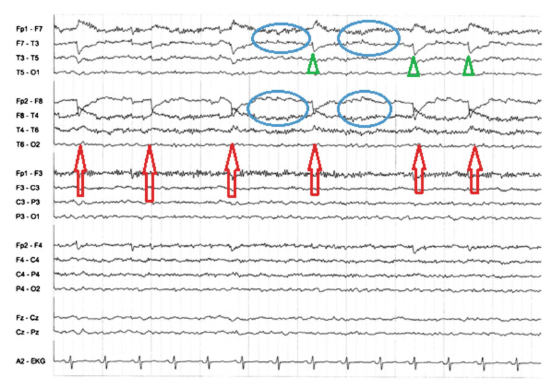

7

Q

Red arrow:

Blue circle:

Green Triangle:

A

Red arrow: Saccadic movements to left

Blue circle: Rightward eye movements(compensatory)

Green Triangle: lateral rectus spike